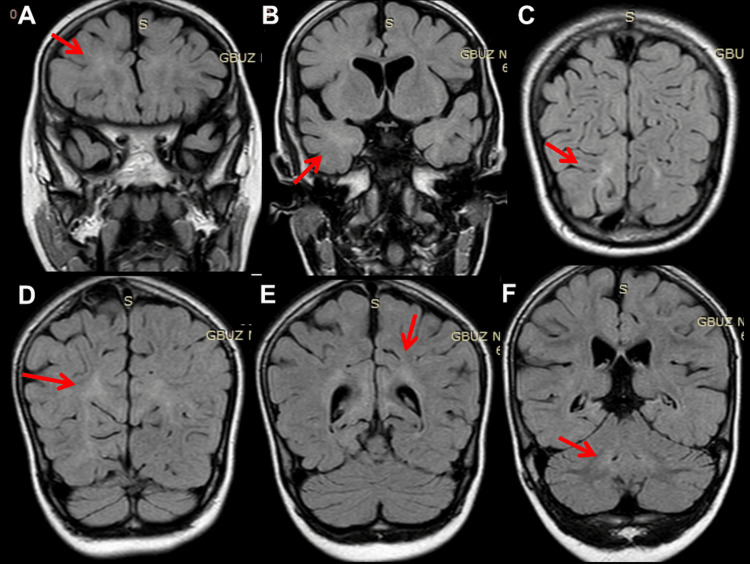

At 12 months of age, she experienced a second SE, again terminated by DP, hydroxy-butyrate, and TP. VPA was switched to phenobarbital (PB). EEG at 15 months showed general slowing, delta activity across the occipital projections, and regional spikes along with delta bursts over O2-T6. At 16 months of age, she suffered a third SE, so PB was switched to oxcarbazepine (OXC), which was discontinued after seven days for ineffectiveness and replaced with perampanel (PER) in monotherapy (Table 3). EEG showed general slowing and focal seizure activity across F3-C3 associated with the eye version to the right. Post-ictal lethargy and decreased motivation occurred. Neurological evaluation after recovery revealed generalized hypotonia, discoordination, unstable eye contact, drooling, open mouth, and ankle contractions. She liked watching cartoons and playing with water. At 27 months of age, clonazepam (CZP) was added to PER with no beneficial effect (Table 3). Subsequently, ethosuximide (ESM) was added to PER but discontinued after 14 days due to ineffectiveness (Table 3). Cerebral magnetic resonance imaging (MRI) at 27 months of age showed bilateral diffuse cortical and subcortical atrophy (Figure 1) and incomplete myelination (Figure 2). At 33 months of age, levetiracetam (LEV) was tried but discontinued after four weeks because of ineffectiveness (Table 3). At 34 months of age, clobazam (CLB) was added to PER but stopped because daily seizures recurred. At 36 months of age, there was still no head control, but she had periodic torticollis to the left, tetraspasticity, increased tendon reflexes, positive pyramidal signs, and widespread hyperkinesia most pronounced in the left shoulder and unrelated to EEG activity. Topiramate (TPM) and hydrocortisone were started and PER was discontinued, stopping seizures for the next 40 months (Table 3). At the age of 40 months, she was switched to therapy with PER and TPM (Table 3).

The index patient also presented with intractable epilepsy, myocloni, psychomotor regression, tetraspasticity, and torticollis. Epilepsy presented with generalized tonic-clonic seizures and focal seizures. Myocloni were not associated with epileptiform discharges. Various seizure types have been reported in NARS2-related disorders. These include focal, generalized, epileptic spasms, infantile spams, myoclonic seizures, absences, and SE [ref. 1]. EEG findings can range from background rhythm slowdown, focal or multifocal spikes/multiple spikes, and hypsarrhythmia [ref. 1]. Cerebral imaging may show hydrocephalus, cortical and subcortical atrophy, white matter lesions, basal ganglia lesions, or subdural hematoma [ref. 1]. The index patient benefited most from VPA, steroids, and PER. All other AEDs were ineffective or only temporarily effective.